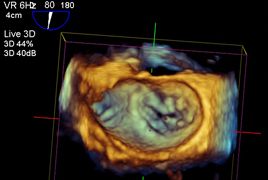

Transösophageale Echokardiographie (TEE)

An unserer Klinik führen wir jährlich rund 1500 intraoperative und intensivmedizinische transösophageale Echokardiographien durch. Hierbei kommen sowohl die 2D als auch die 3D Echokardiographie regelmäßig zum Einsatz.